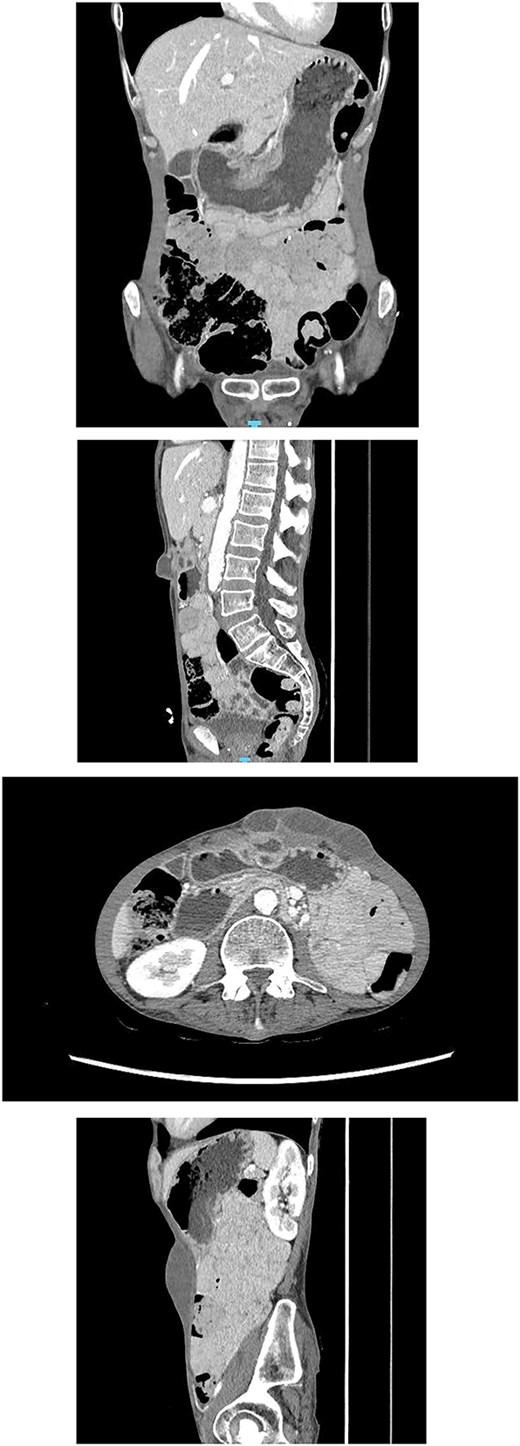

Repeated CT abdomen with oral contrast (Fig. 4): No oral contrast leak into the upper anterior abdominal fluid collection.

Repeated CT abdomen with oral contrast revealing no oral contrast leak into the upper anterior abdominal fluid collection.